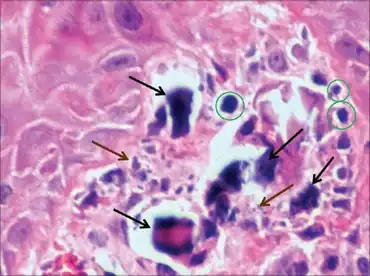

| Histologic sample of subepidermal calcified nodule | |

Calcifications ranged from large amorphous deposits arrows, well-formed small spherules green circles to small fine granules arrows